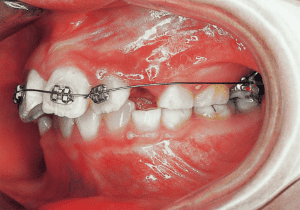

15 At second stage treatment initiation 9-21-’91 Observing eruption of maxillary canines

16 Four months post-second stage treatment initiation 2-29-’92 Currently using headgear on maxill

In the maxilla, insufficient space for canine eruption was inevitable, necessitating extraction as part of the treatment plan. The maxillary first premolars on both sides were extracted during routine observation to create space for canine eruption (14). Eventually, the canines erupted and settled into relatively favorable positions (15,19,20). In the mandibular dentition, crowding was also present, leading to extraction of the mandibular first premolars on both sides. Treatment with full bracket was then initiated (17).